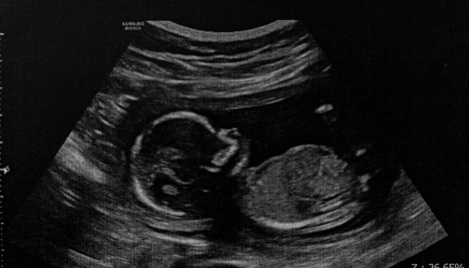

Idaho will require schools to teach fetal development, show ultrasound video to students

Idaho's Republican Gov. Brad Little has signed a law requiring schools to teach about fetal development, a move proponents believe will enable children in the state to learn that life begins at conception.